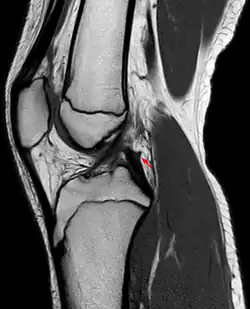

- das Ligamentum meniscofemorale posterius (auch Ligamentum Wrisberg) hinter dem hinteren Kreuzband und

- das Ligamentum meniscofemorale anterius (auch Ligamentum Humphry) vor dem hinteren Kreuzband verlaufend.[2][3][4]

In der MRT muss der Verlauf der Ligamenta meniscofemoralia berücksichtigt werden, um eine Verwechslung mit einem verlagerten Anteil des Außenmeniskus bei einem Riss desselben zu vermeiden.[10]